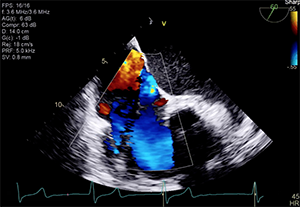

Transthoracic and transesophageal echocardiography (TEE) confirmed severe functional TR due to annular dilation associated with RV and right atrial enlargement. Mild leaflet tethering, predominantly septal, was also appreciated. The coaptation gap was < 10 mm and the jet origin was predominantly central with extension toward the anteroseptal commissure. Image quality in both transesophageal midesophageal and transgastric windows were good (Videos 1–5).

Dr. Taramasso: The quality of TEE is really high, and the short axis of the tricuspid valve shows an anteroseptal location of the jet with an acceptable coaptation gap, which is ideal anatomy for edge-to-edge repair. Both MitraClip and Pascal have independent grasping that could be helpful to catch the septal leaflet, which is tethered. Because the annulus is dilated, annuloplasty could be also a good choice.

Dr. Hahn: The current images suggest a relatively small coaptation gap, although the severity of TR is likely “massive.” In the setting of normal RV function, a number of devices could be used, including an annular device (Cardioband) or leaflet device (TriClip [Abbott] or Pascal). These patients could also be treated with an orthotopic replacement device, but less is known about these devices.